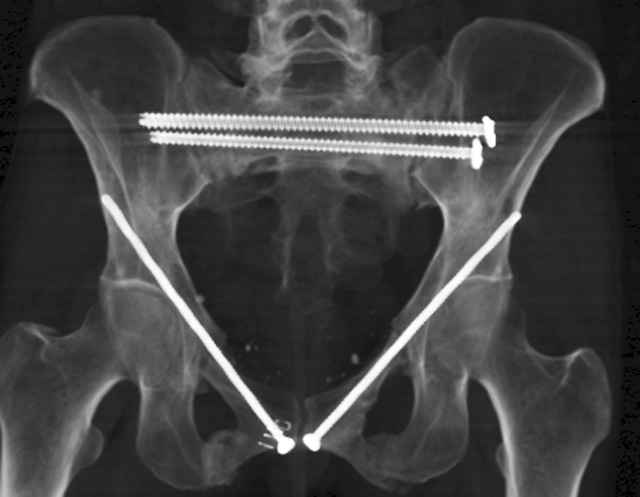

Percutaneous Fixation

(B) Ramus-Retrograde

2 TransIliac-TransSacral

Upper Segment

mlcr